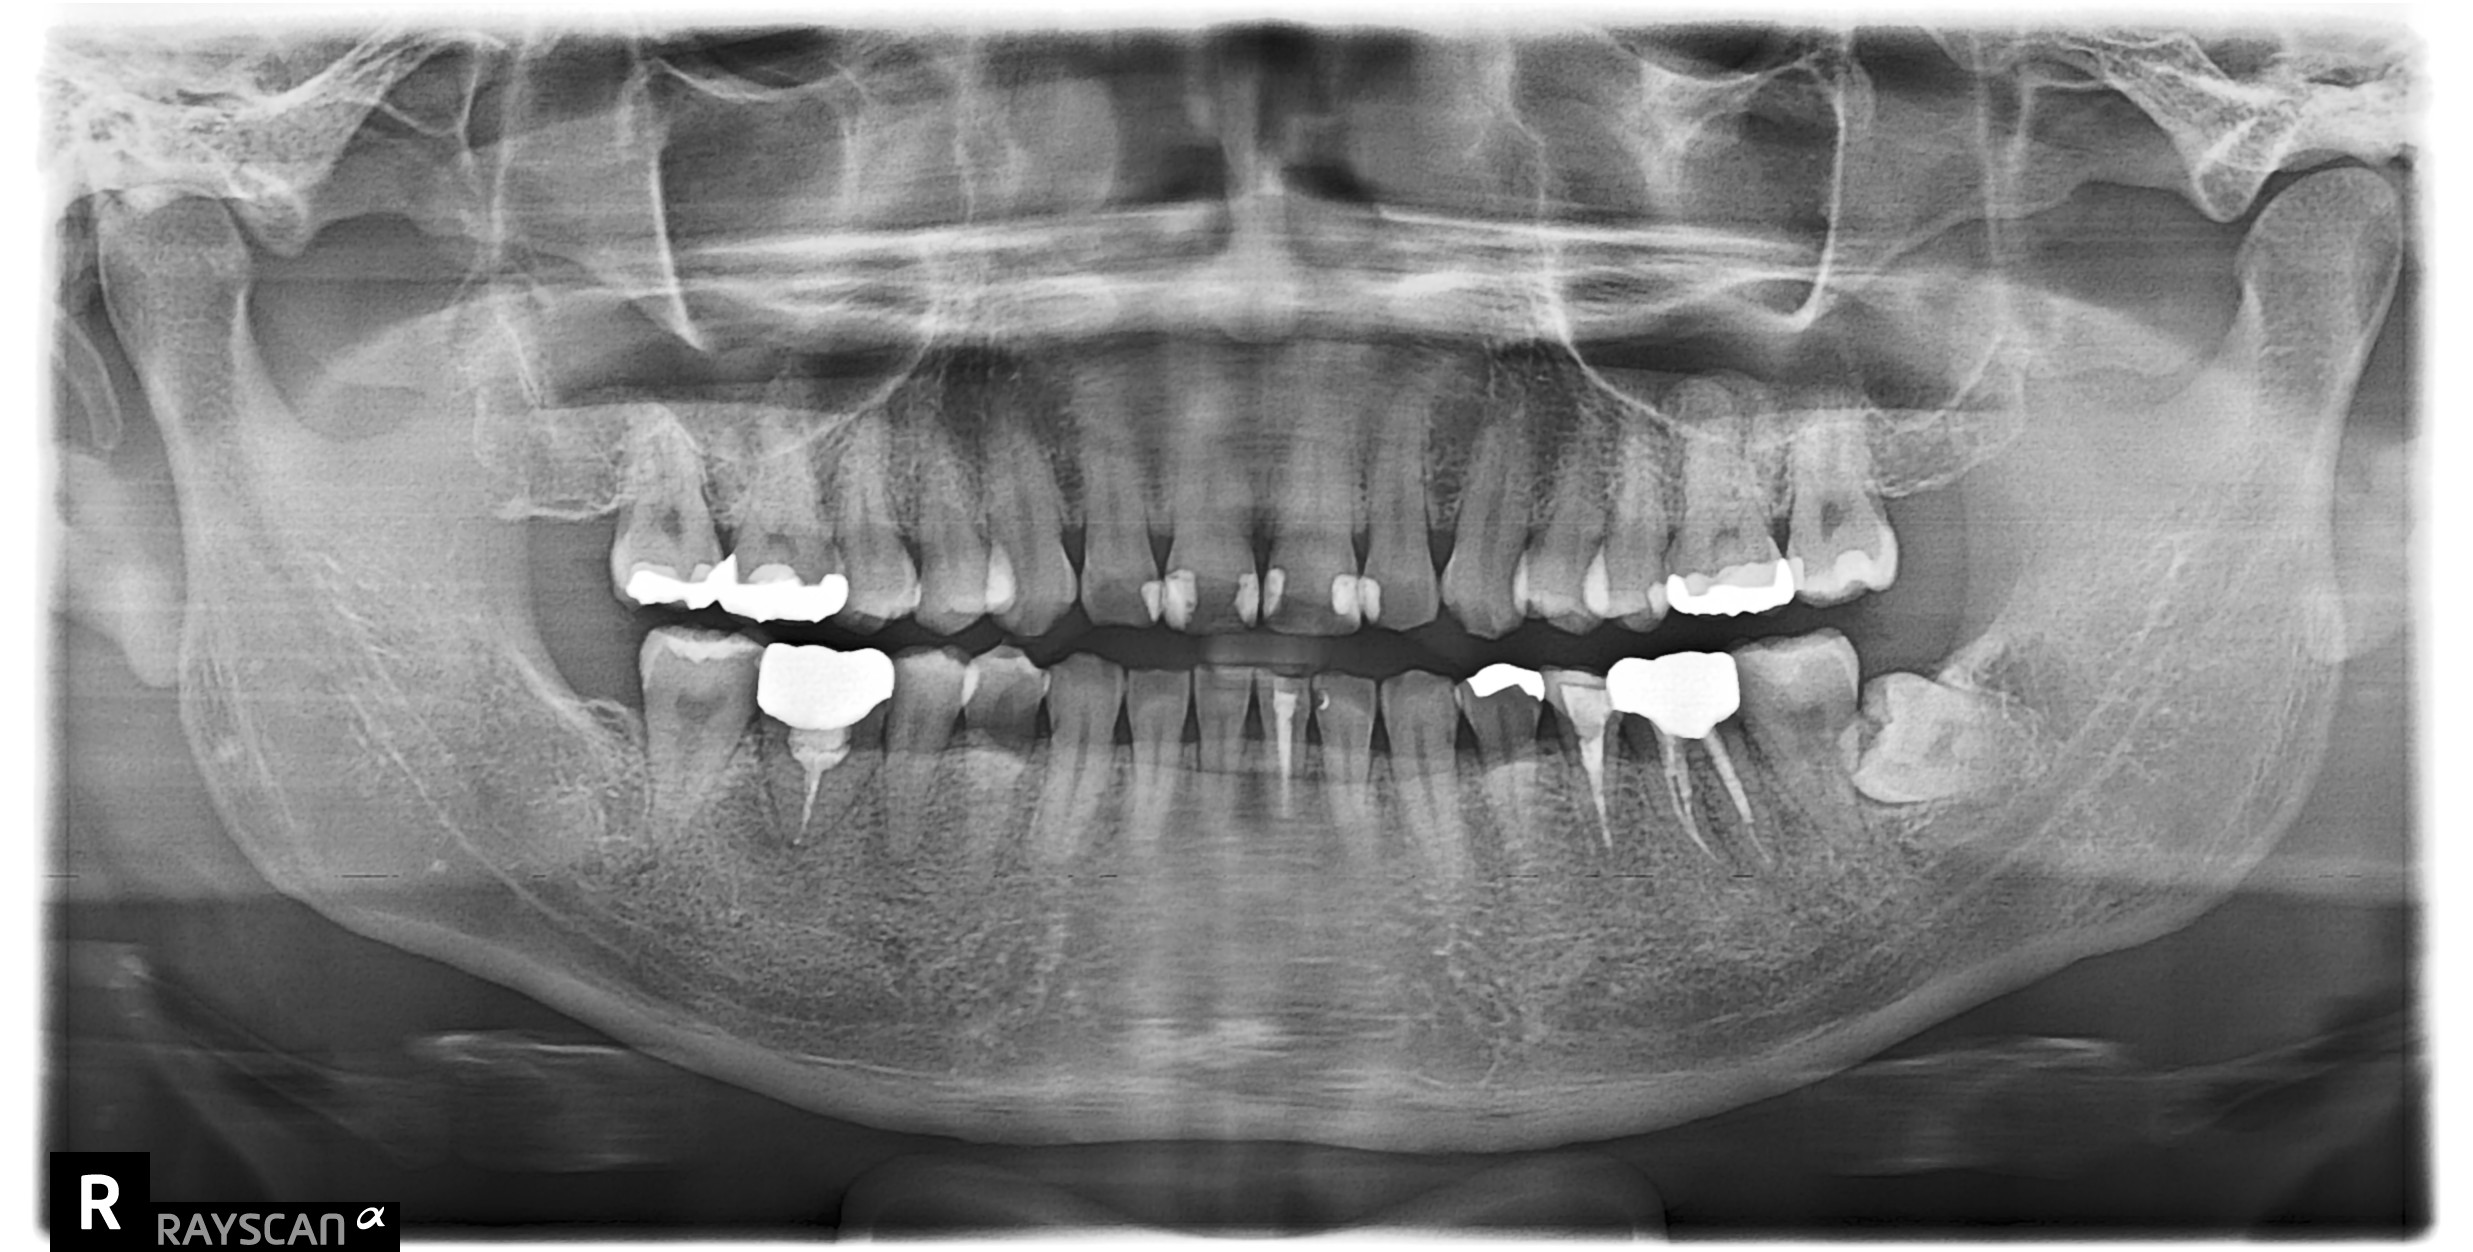

術後 半年

周囲の歯を保護することができ、レントゲンでは周囲の骨も回復してきておりました。